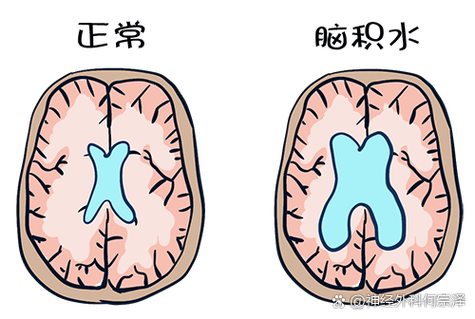

脑积水的症状

脑积水是由于脑脊液循环通路发生阻塞,导致脑脊液在脑室系统内过多积聚,使脑室扩大,从而压迫周围正常的脑组织,脑积水的症状发展通常比较缓慢,呈进行性加重,但急性脑积水(如脑出血后突然阻塞)则发展迅速。

脑积水的症状主要与颅内压增高脑组织受压有关,具体表现因发病年龄和病情急缓而异。